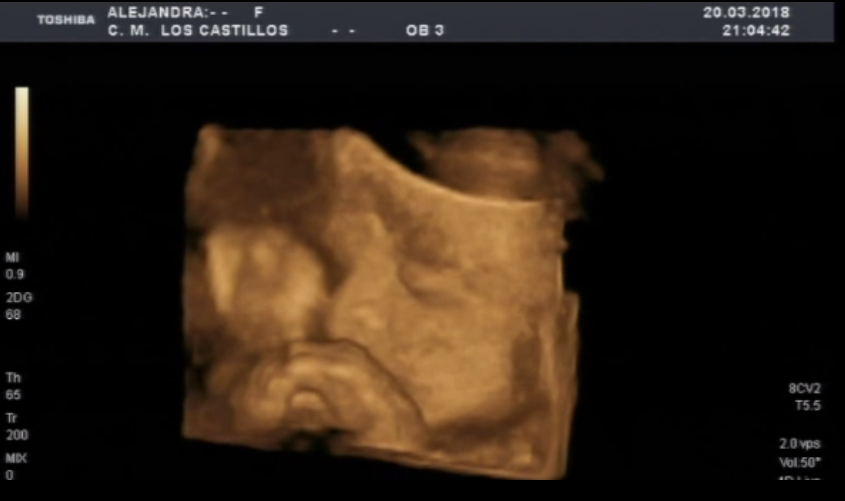

Llaman al teléfono SOS de +Futuro. Son las 11 de la noche, son un grupo de misioneras de extremadura. Acogen y educan a chicas desahuciadas y en riesgo de exclusión social. Una de sus chicas, ya mayor de edad que se ha ido a vivir con la madre de su novio esta de 26 semanas de embarazo. Quieren que aborte todo su entorno. Ella no. Un médico y el abortorio de Badajoz dicen que su niño viene con hidrocefalia. Afirman con contundencia que la madre corre peligro de morirse. (fotos de una ecografía de Alexia, la hija de dos voluntarios de la asociación de 26 semanas).